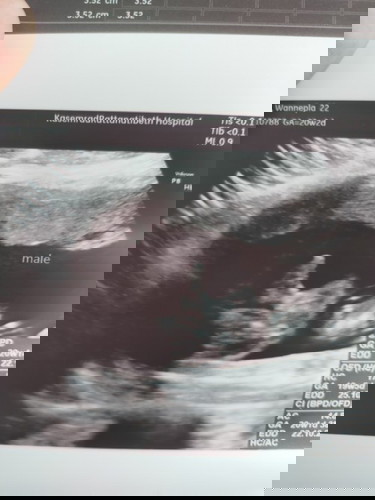

เหมือนกันค่ะ นอนอ้าซ่าเลย ไม่ต้องลุ้นไม่ต้องเดา คุณหมอยังบอกไม่หุบให้ลุ้นเลยหมุนไปทางไหนก็เจอ

บ้านนี้ก็ชัดเจนค่า เป็นคนเปิดเผยแต่เล็กแต่น้อย😆

ดูไม่ออก แต่ดูในจอเป็นผู้ชายคับ เห็นจู๋ชัดแจ๋ว 🤣

เป็นเด็กเปิดเผยค่ะ อ้าขาให้เห็นกันชัดๆ ไปเลย 55555

บ้านนี้ก็โด่เลยค่ะแม่ เห็นก่อนสิ่งอื่นใด😆

ในภาพกี่วีคค่ะ บ้านนี้ 13+4 อยากรู้บ้าง